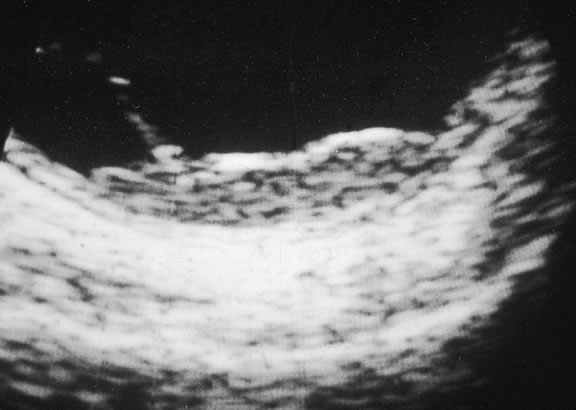

Ultrasonography can support the diagnosis of ciliary body or choroidal melanoma and is a particularly helpful way of disclosing tumors in eyes with opaque media.54 Ultrasonographic studies can alsodemonstrate areas of extrascleral extension. A scan ultrasonography shows a high internal spike and low internal reflectivity. B scan ultrasonography shows characteristic acoustic hollowness and choroidal excavation (Fig. 23). Hemangiomas and metastases usually appear acoustically solid because they contain multiple acoustic interfaces.

Fig. 23. B-scan ultrasound, choroidal melanoma.

The diagnosis of intraocular metastasis usually is made by slit lamp biomicroscopy and ophthalmoscopy in the patient who has been carefully questioned about a past medical history of cancer. Ancillary techniques such as intravenous fluorescein angiography and ultrasonography often can assist in making the diagnosis. Metastases generally begin to show hyperfluorescence in the late venous phase fluorescein angiography, somewhat later than most melanomas or hemangiomas.48,54 Metastases have many acoustical interfaces because they are composed of nests, cords, and island of tumor cells surrounded by stroma. Hence, they show high internal reflectivity on A scan ultrasonography and appear acoustically solid in B scan, characteristics they share with hemangiomas (Fig. 49). In cases in which the results from other studies are equivocal, cytopathologic examination of material obtained by fine-needle aspiration biopsy may establish the diagnosis.82,83

Fig. 49. B-scan ultrasound, choroidal metastasis. Placoid tumor has high internal reflectivity.